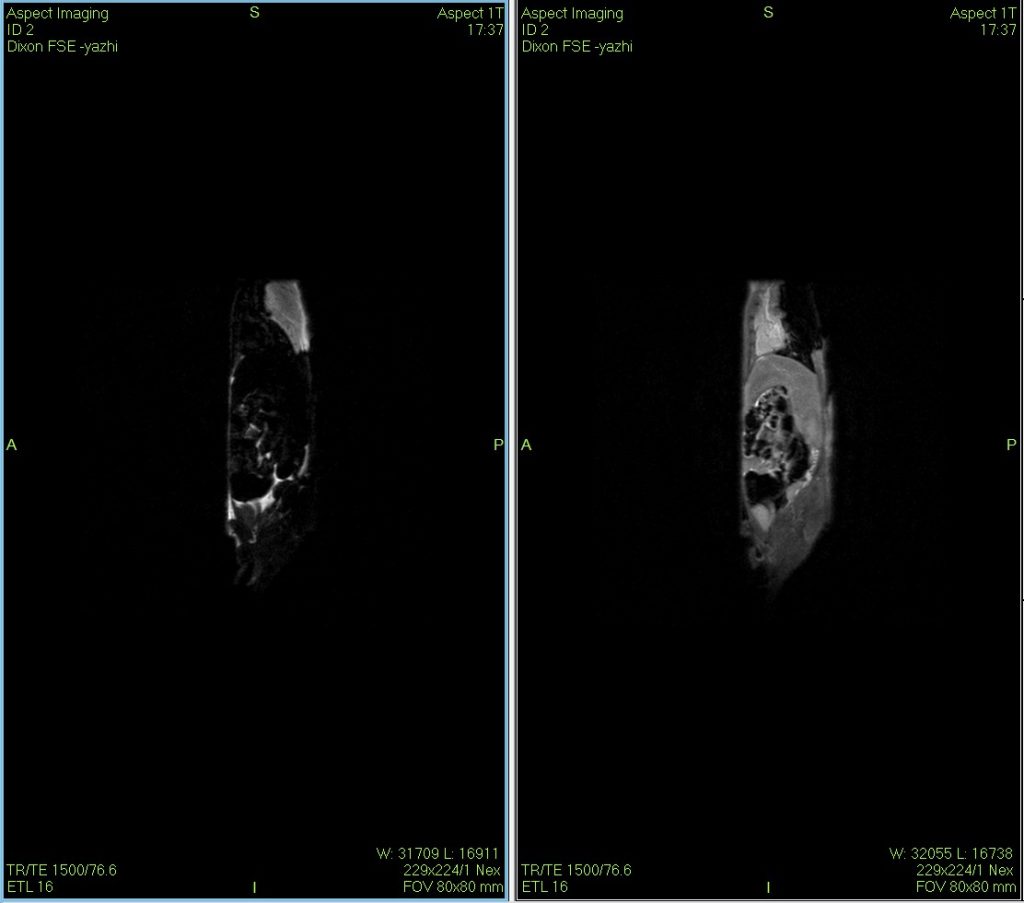

Dixon技术可用于多方面研究,包括肝脏脂肪研究、肥胖与代谢性疾病、脂肪肿瘤、肾脏、肝脏局灶性病变等。

小鼠核磁共振Dixon水脂成像图

Dixon水脂分离技术是一种使用的核磁成像技术,在某些动物疾病模型的诊断、鉴别与治疗过程的评估上具有一定的独到之处。